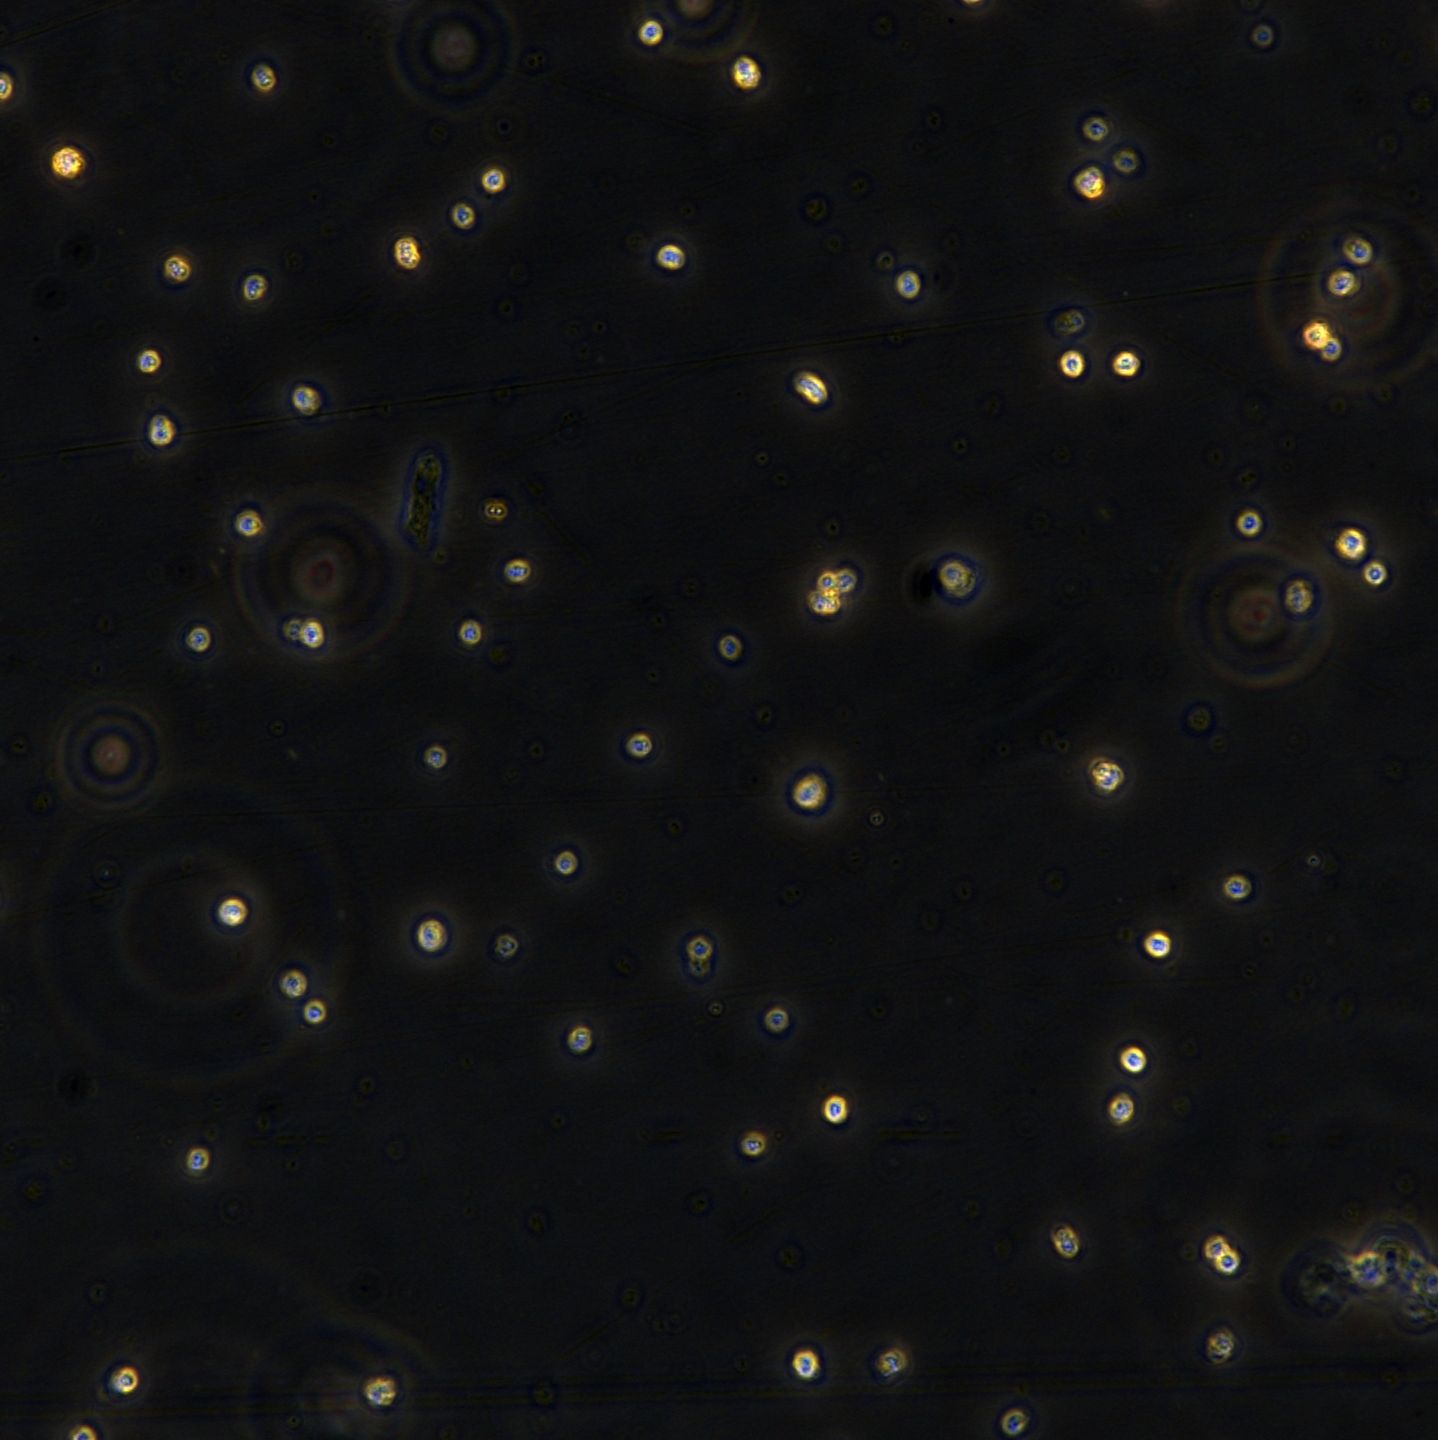

悬浮生长(Suspension)

分析核型,而且能分选出不同类型的染色体,做成人类每条染色体的 DNA 文库,可用于人类基因组研究、遗传病和癌症的诊断的研究。 免疫学研究 结合免疫荧光方法,流式细胞术可辨认和计数带有不同表面特异性抗原的细胞,例如用荧光素标记的免疫球蛋白鉴别T和B淋巴细胞,根据细胞表面抗原的不同,进一步分辨出不同的 T 和 B 淋巴细胞亚群,以及测定每个细胞所带抗原的数量、密度及其动力学参数等。也可用流式细胞分选技术将带有「+」和不带有「-」的某种特异抗原的细胞群体分类收集,供研究其功能特性。 流式细胞